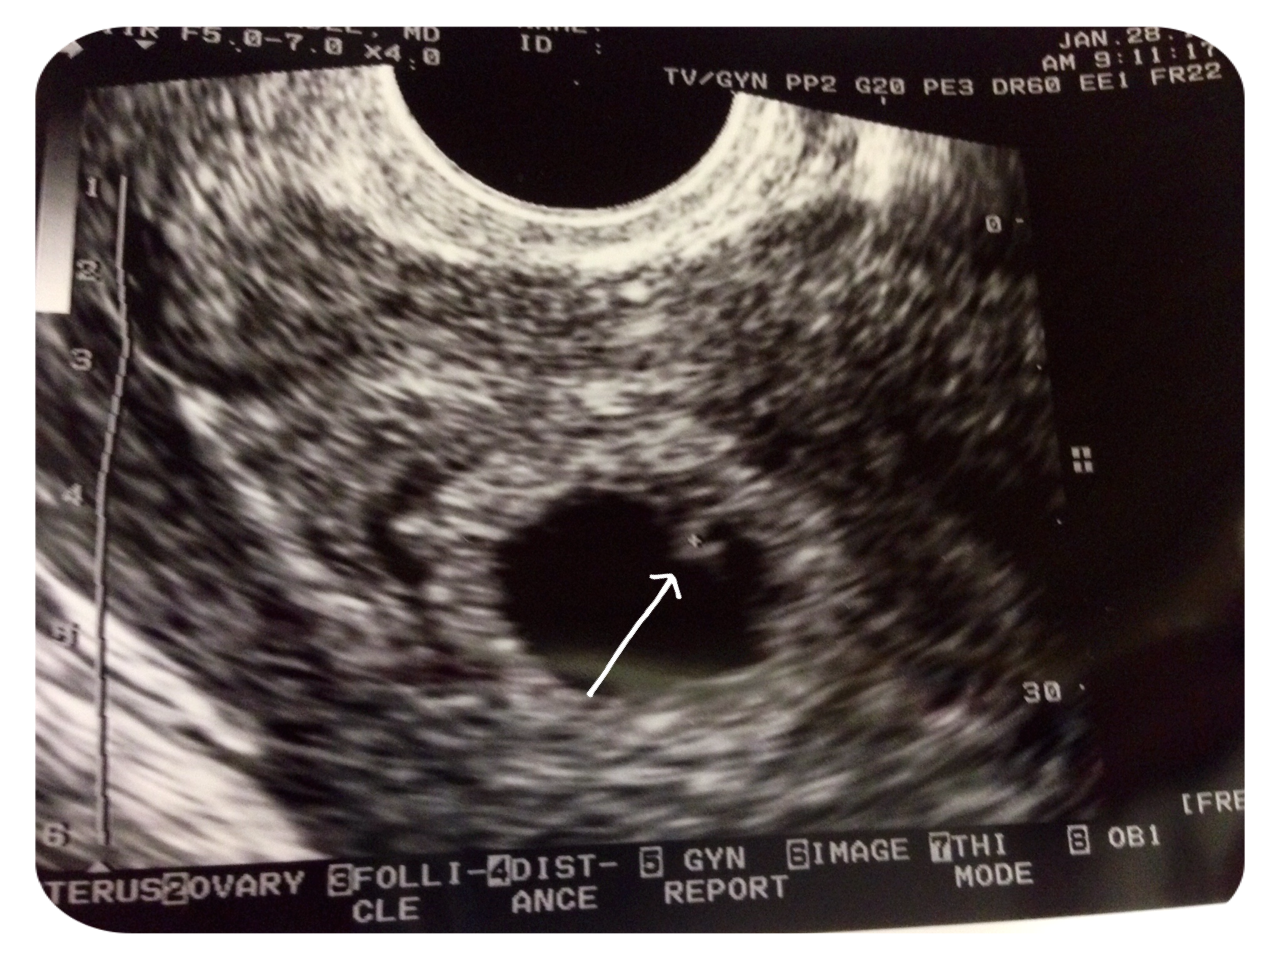

Got to the dr, and she did a physical exam, but saw no other spots of blood or clots. Went ahead to do an u/s and saw nothing concerning.

And then we got to see the tiny flickering little heartbeat on the monitor! I totally teared up and hubby squeezed my hand and smiled.

Measuring about a week behind my LMP date, but will get more confirmation when I transfer and go see my new OB next week (current dr is only GYN).